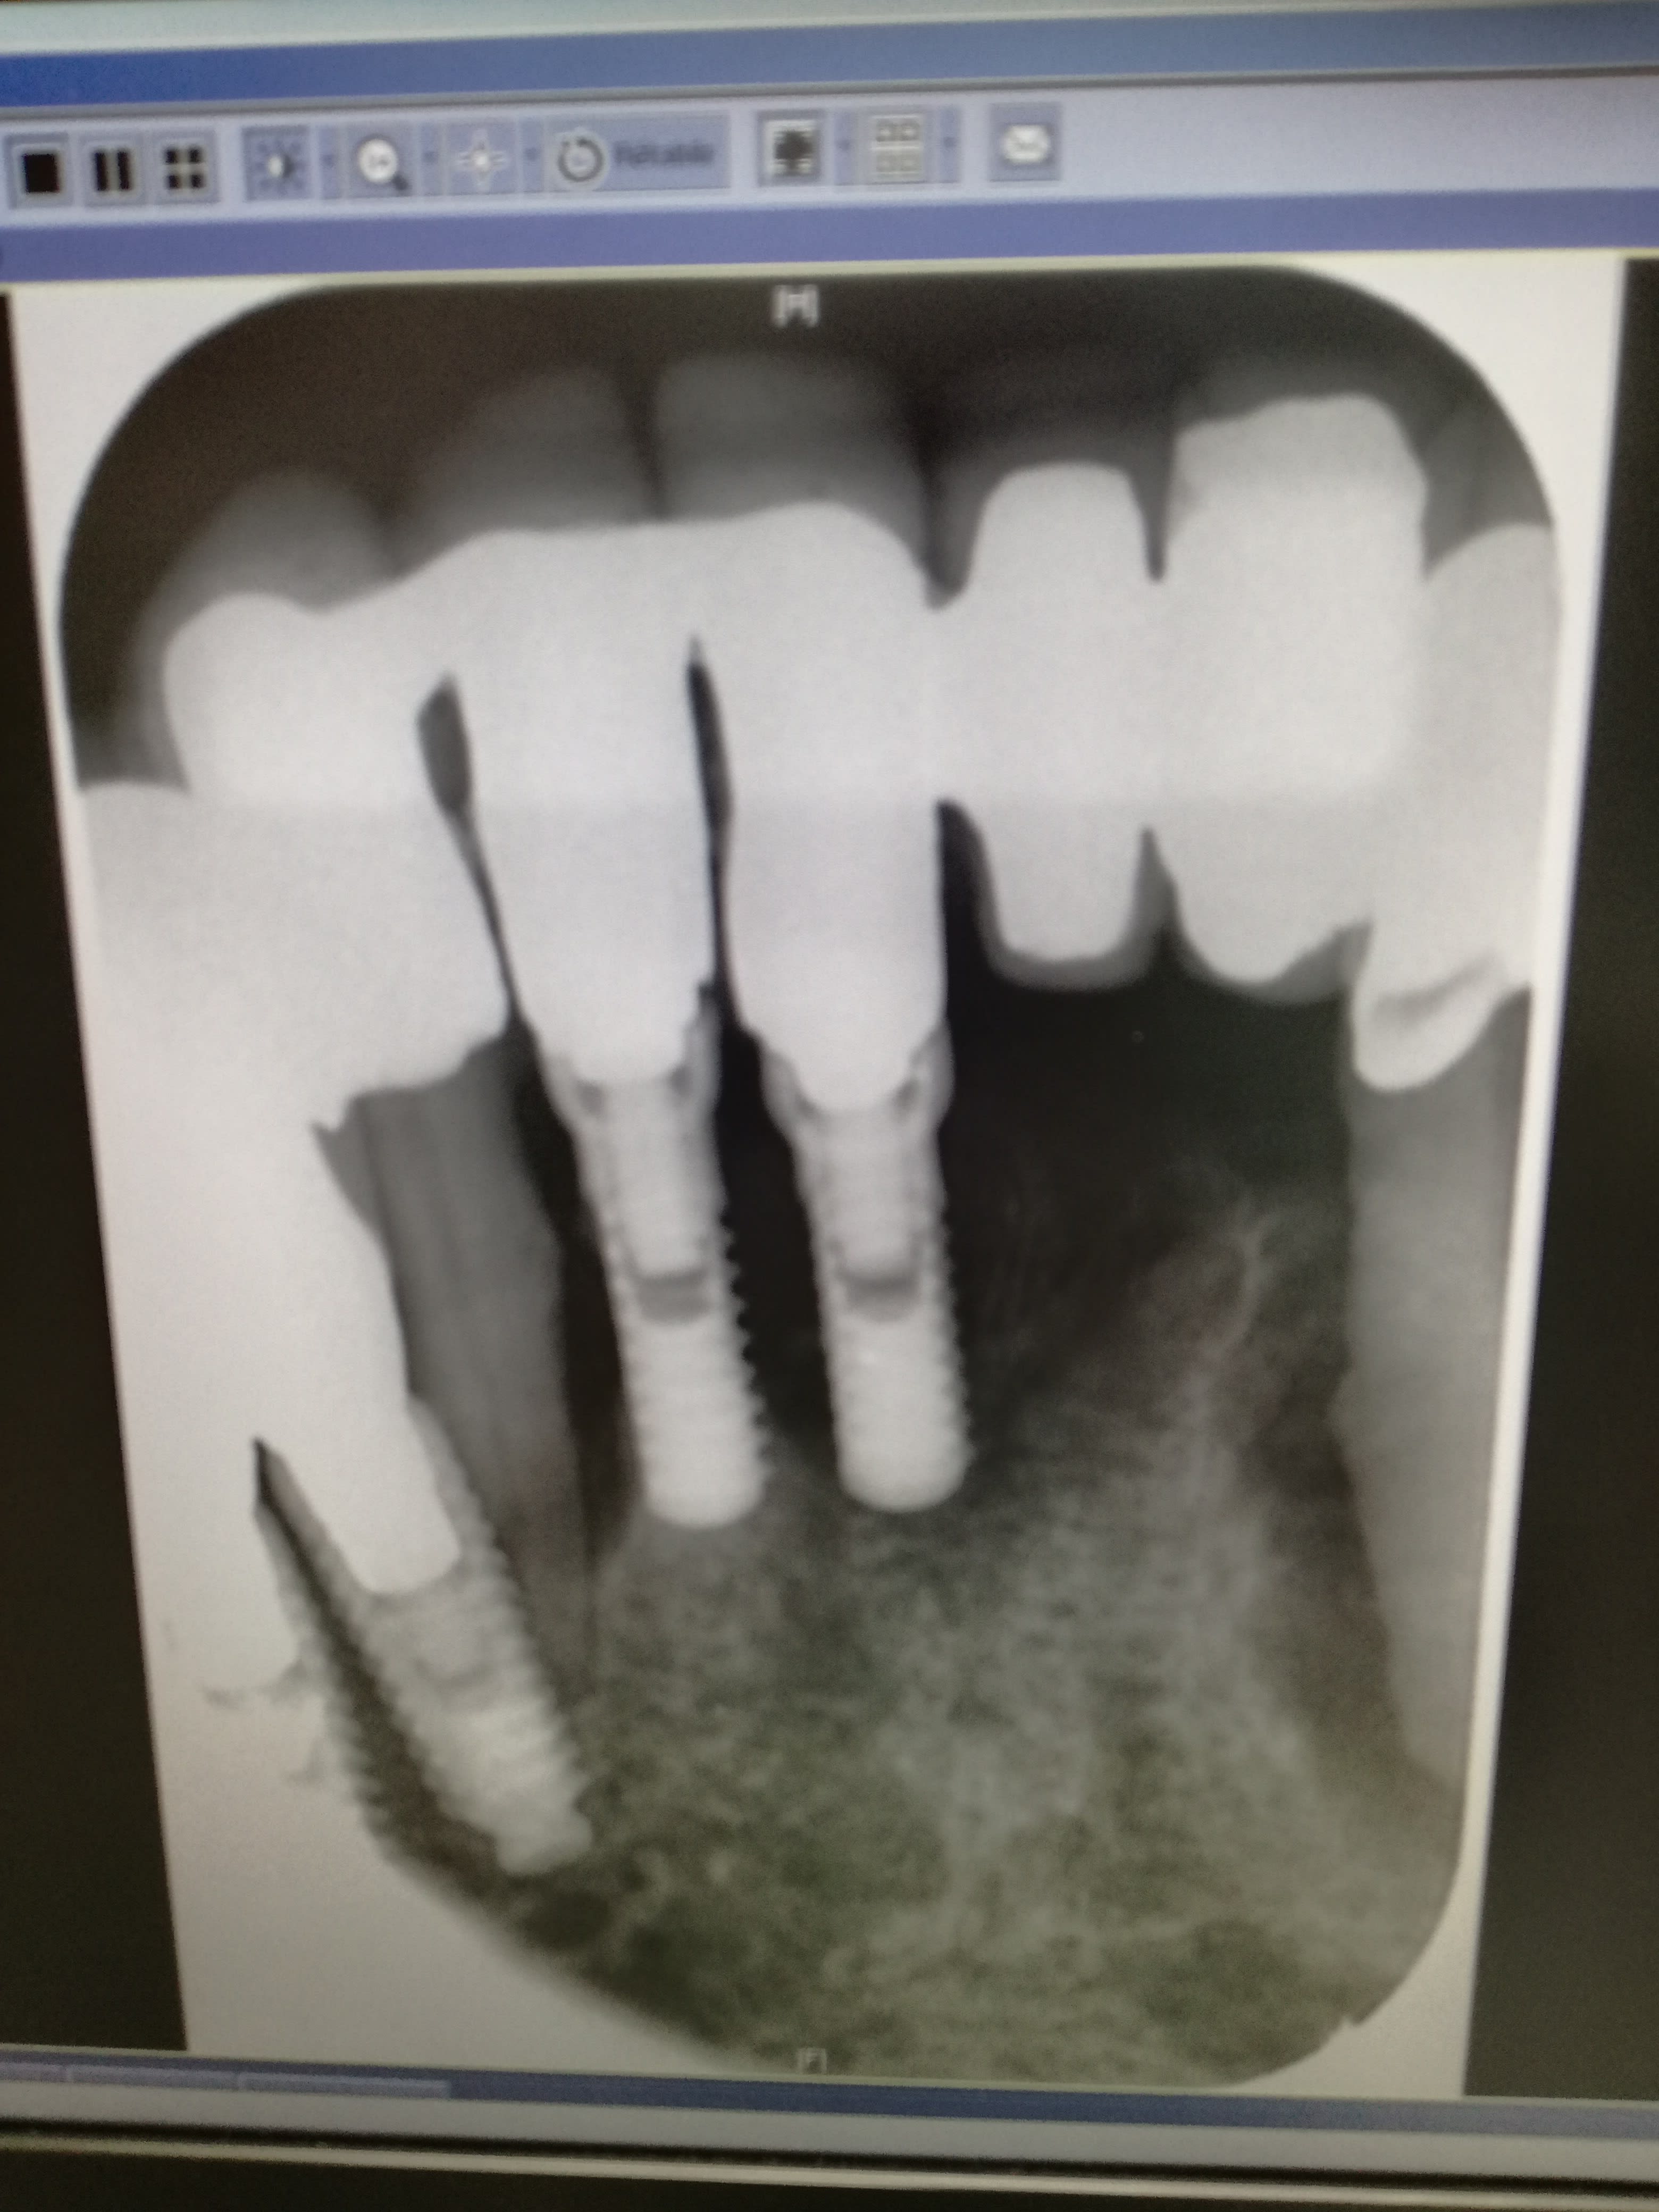

Allez, pour le plaisir des mirettes et pour vous faire rire un coup (même si franchement quand j'ai du expliquer la situation à la patiente qui était adressée pour le traitement d'un kyste sur 33 ni elle ni moi n'étions trop heureux), je vous propose un nouveau cas. A mon grand regret je n'ai pas l'historique du dossier ce coup ci, juste une visite de la patiente. Vous aurez moins de réflexion, mais l'originalité du traitement vaut son pesant de cacahuètes.

-L'original bridge en extension implanto-porté (46)45-44

-Le (trop) audacieux bridge antérieur implanto-dento-porté sur dents vivantes et son assortiment de lésion endoparodontale et de péri-implantite

-Et enfin ma préférée, l'extravagante couronne implanto-dento-portée en 36, sa lésion endoparo et sa probable fracture radiculaire

Autrement j'ai quand même une question pour vous, comment le praticien a-t-il réussi son coup pour monter une infrastructure coronaire en 36 qui s'appuie sur les deux supports à la fois avec des axes divergents?

L amputation de la racine mésiale de 46 et la racine distale solidarisee sur l implant... Mais c est de l art.

Oui mais par quel protocole tu arrives à solidariser çà ? J'ai du mal à concevoir le type d'empreinte qui a permis de monter un truc solidarisant les deux éléments, et le truc en lui même. IL faudrait une moitié tenon radiculaire, une moitié pas de vis pour implant? Mais du coup impossible à visser. Ou alors c'est juste scellé dans l'implant et la dent comme un simple inlay core à clavette?

Un pilier implantaire a la place de la racine mésiale et en distal un inlay core. Une double CCM solidarisee par dessus le tout... De la dentisterie du Turfu.

Enfin quoique... Je sais pas trop ce qui rentre dans la connexion de l implant... Si ça se trouve c est juste une pièce scellé dans l implant. Du très très haut niveau.

Oui, je l'avais envisagé ce montage sur 2 supports avec une espèce de double CCM, le top niveau.